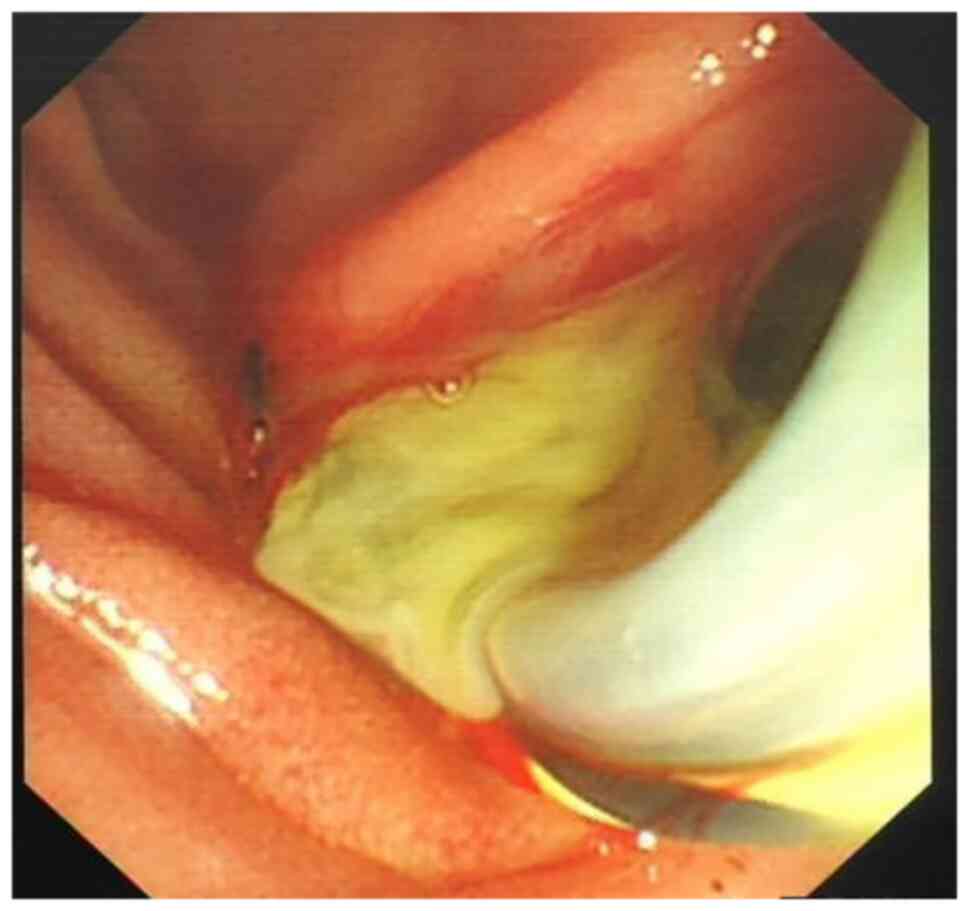

Charcot's triad, shock and central nervous system depression were observed in 14 of 47 patients with AOSC. A total of 33 patients were found to have between two and four features of Charcot's pentalogy, including one patient with coma. After having performed clinical and endoscopic minimally invasive treatments, purulent bile outflow was observed in 47 patients with AOSC (Figs. 1 and 2), including 41 cases of common bile duct stones (Figs. 3 and 4). The end-stage tumors included bile duct malignancy in four cases and pancreatic cancer in two cases and the clinical symptoms were significantly improved. In this group, on day 7 after endoscopic treatment, blood inflammatory indexes and liver function were found to be significantly improved the most of the group compared with the measured values at admission: The level of PCT decreased from 8.95±15.26 to 0.42±0.37 ng/ml, the level of CA-199 was reduced from 635.04±907.76 to 164.68±475.78 kU/l and that of ALT was decreased from 190.96±105.91 to 50.56±20.33 µmol/l. The value of the direct bilirubin test was decreased from 62.21±36.23 to 30.64±15.40 µmol/l and these differences were found to be statistically significant (P<0.05 or P<0.01), as shown in Table VII. Out of the total of 47 patients, 16 cases involved the use of ERCP and ENBD, 17 cases included the use of ERCP, EST and ENBD, 14 cases included the use of ERCP and ERBD, and 28 cases included the use of ERCP for stone extraction. During ERCP examination, purulent bile was discharged from the bile duct. A total of three patients underwent secondary ERCP (Table VI). Out of the total cases, 35 (74.5%) showed positive results in the bile culture. The predominant bacterium species identified were Gram-negative bacteria, with Escherichia coli being the most frequently observed in 11 instances (31.4%). Klebsiella pneumoniae was detected in seven instances, accounting for 20% of the cases. Pseudomonas faecium was identified in five cases (14.3%), Enterococcus faecium in four cases (11.4%), Pseudomonas aeruginosa in four cases (11.4%), Staphylococcus aureus in three cases (8.6%) and Enterococcus casselifavus in two cases (5.7%). There was one case of both E. faecium and E. coli (2.9%), two cases of K. pneumoniae and Candida albicans (5.7%), one case of E. faecalis, K. pneumoniae and Enterococcus casselifavus (2.9%), one case of Aeromonas hydrophila (strain found in guinea pigs) and E. faecalis (2.9%), and two cases of E. faecalis and E. coli (5.7%). There were two cases of Citrobacter freundii and Stenotrophomonas maltophilia, accounting for 5.7% of the cases. Additionally, there was one case of E. faecium and C. albicans, which made up 2.9% of the cases. Within 1 to 7 days after treatment, the high fever of 45 of the patients disappeared and their body temperature returned to normal. It was difficult to completely control the infection in the remaining two patients after 7 days of ERCP treatment. One of these patients was an elderly patient (≥80 years old) with a secondary tumor and stenosis of bilioenteric anastomosis complicated with AOSC. Even though the infection was not entirely treated while the patient was in the hospital, the family members requested that the patient be discharged. Another patient with multiple common bile duct stones complicated with sepsis underwent some improvements after a second line of ERCP was performed and was discharged. Within 7 days of treatment, the abdominal pain of 27 patients, and jaundice experienced by 29 patients, were resolved. Hyperamylasemia or acute pancreatitis (mild) occurred in three patients following ERCP, which itself improved after conservative treatments. The average hospital stay per patient was 11.9±4.6 days. Finally, no severe complications, including perforation, bleeding, severe pancreatitis or mortality, were identified for any of the patients.

Figure 2

Large amount of purulent bile.